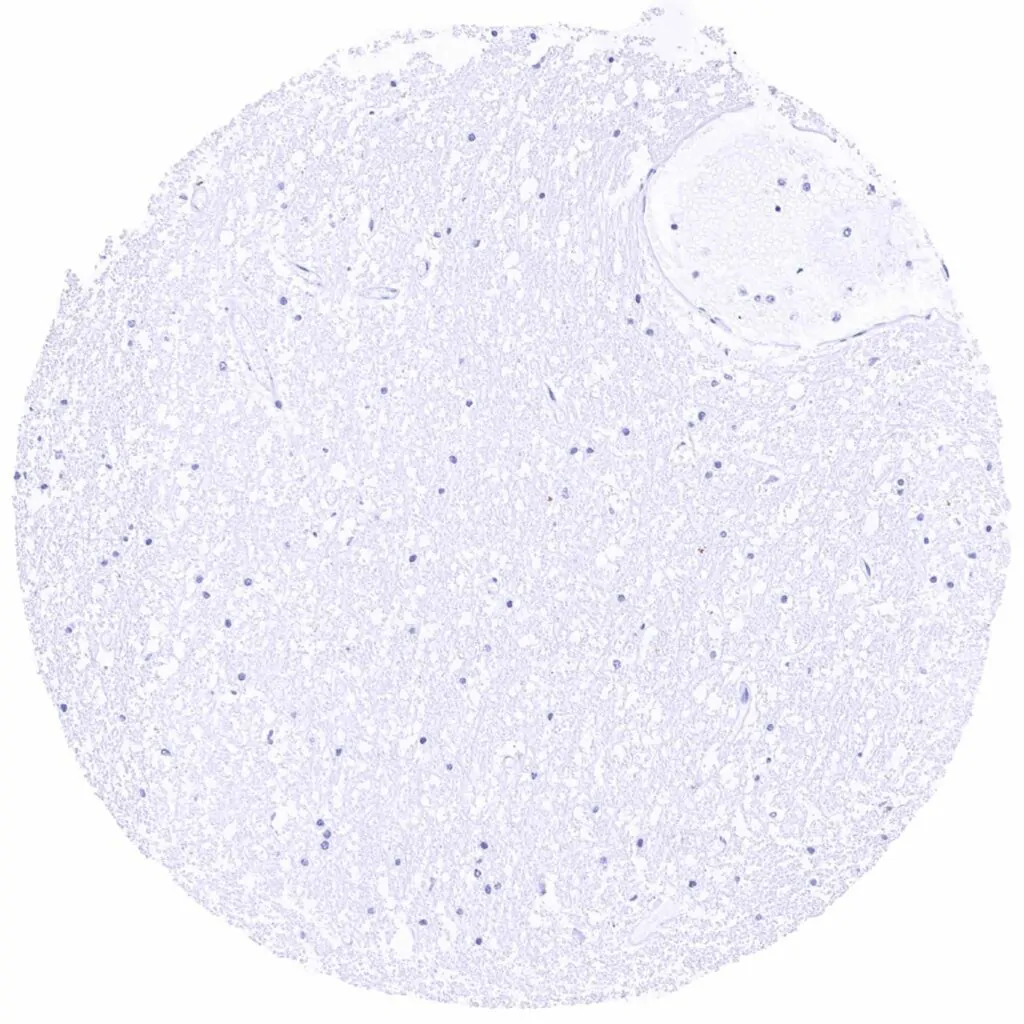

Liver